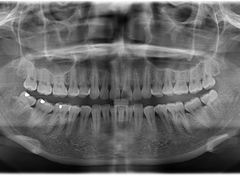

• 瑞尔齿科(南京东路名人诊所)

• -瑞尔齿科(南京东路名人诊所)